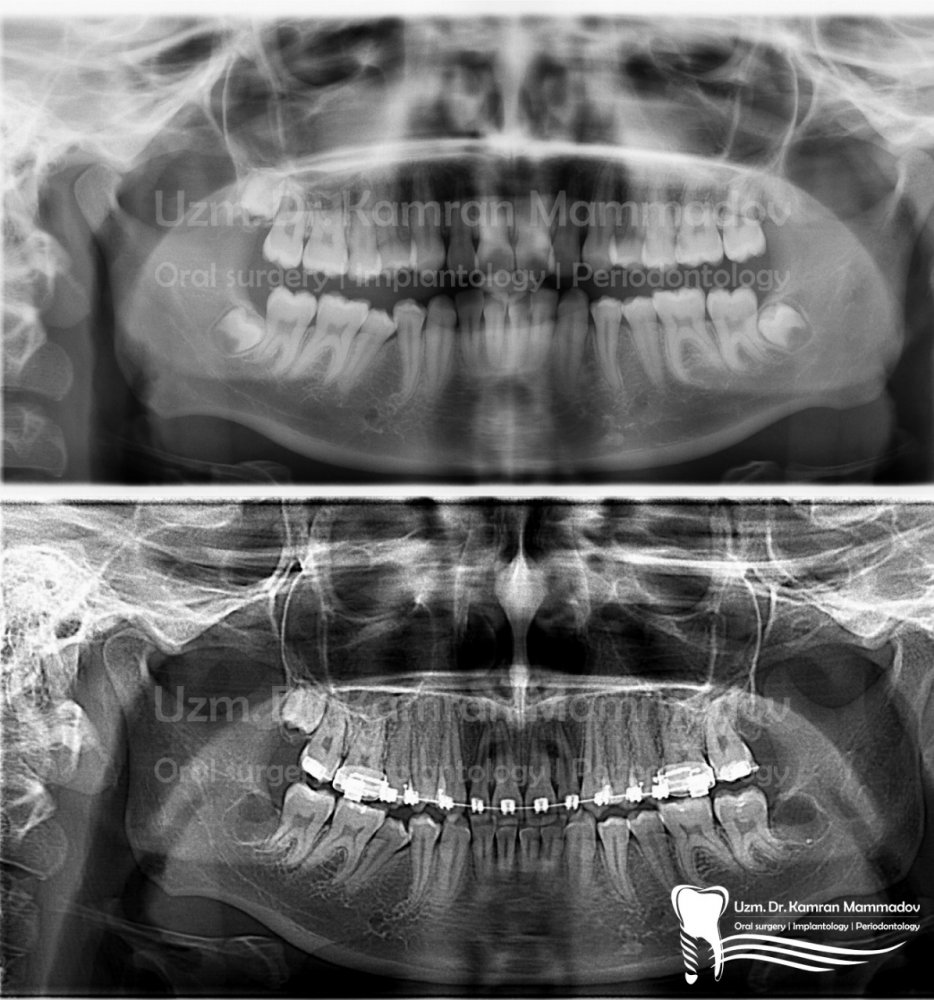

Normal halda insanın diş sırasında hər çənədə iki ədəd olmaqla, ümumilikdə dörd agıl dişi mövcuddur. Ağıl dişinin çıxması bəzi şəxslərdə heç bir kliniki əlamət və ya şikayətə səbəb olmasa da, bir çox hallarda müəyyən kliniki əlamətlərlə öyünü biruzə verir. Bu əlamətlər əsasən çənənin arxa tərəfində təzyiq, çənəni açıb baglama əsnasında agrı və məhdudlaşma kimi özünü göstərə bilir. Bu hallarda mütəxəssis konsultasiyasının önəmi olduqca böyükdür. Belə ki müayinə zamanı cərrah-stomatoloq kliniki və radioloji dəyərləndirmə apararaq dişin dogru pozisiyada yerləşib yerləşmədiyi, dişləmə çıxma ehtimalını, agıl dişinin çənəyə görə ölçüsü və çənə darlıgı kimi durumları dəyərləndirərək tətbiq edilməli olan müalicə taktikasını müəyyən edir.

- Retensiyon ağıl dişinin spontan və ya ortodontik olaraq dişləmə çıxma ehtimalı mövcud deyilsə

- və eyni zamanda digər bir dişin əvəzləyicisi kimi istifadə olunmayacaqsa (transplantasiya və ya ortodontik)